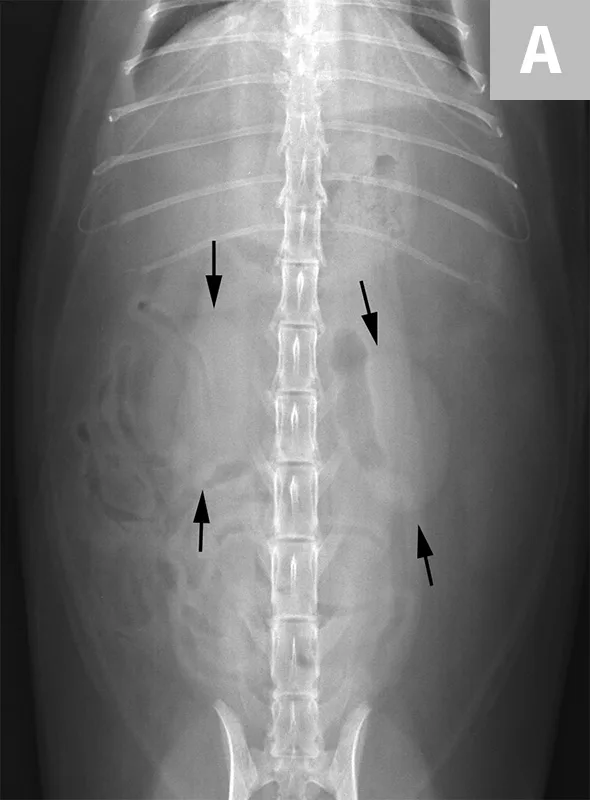

FIGURE 7A

Lateral abdominal radiograph of a cat with multiple, small, oval mineral opacities superimposed over the ventral aspect of the retroperitoneal space (arrows). These mineral opacities are arranged linearly extending from the caudal aspect of the kidneys to the level of the urinary bladder.